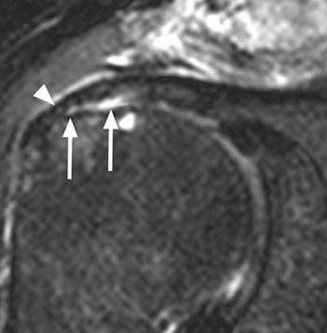

Identify the muscles that compose the force couples in the transverse and coronal planes? CASE 3 A 35-year-old male has had left shoulder pain for 4 months, ever since a low-speed motor vehicle accident (MVA). Physical examination demonstrates preserved range of motion but pain and some weakness with Jobe’s testing. His imaging is shown in Figure 2–8.

Figure 2–8_Reproduced with permission from Stadnick ME. _Partial Rotator Cuff Tears. MRI Web Clinic. 2007 (Apr).

What is the most likely diagnosis?

The correct answer is (A). These are best diagnosed on an MRI as seen in the imaging provided; addition of intra-articular contrast can further improve this study. Answer B, full-thickness rotator cuff tear, is incorrect as the bursal side of the tendon can be seen to be in continuity. Answer C, a SLAP lesion, will be visualized as a labral tear on a coronal MRI and will be found at the biceps root. Answer D, an ALPSA lesion, will be most clearly seen on an axial MRI. It is a variant of a Bankart lesion where the labrum is displaced medially and inferiorly rolling down the glenoid neck underneath the periosteum.

MRI remains the most popular imaging modality for diagnosing rotator cuff tears. Normal rotator cuff tendon appears dark on both T1 and T2 sequences. Tears may be noted as being full-thickness, articular-sided, bursal-sided, or intrasubstance. They are visualized as a disruption in the regular contour of the tendon and increased signal intensity on T2 sequences. Occasionally, an MR arthrogram may provide additional information regarding a cuff tear, although this is not routinely ordered.